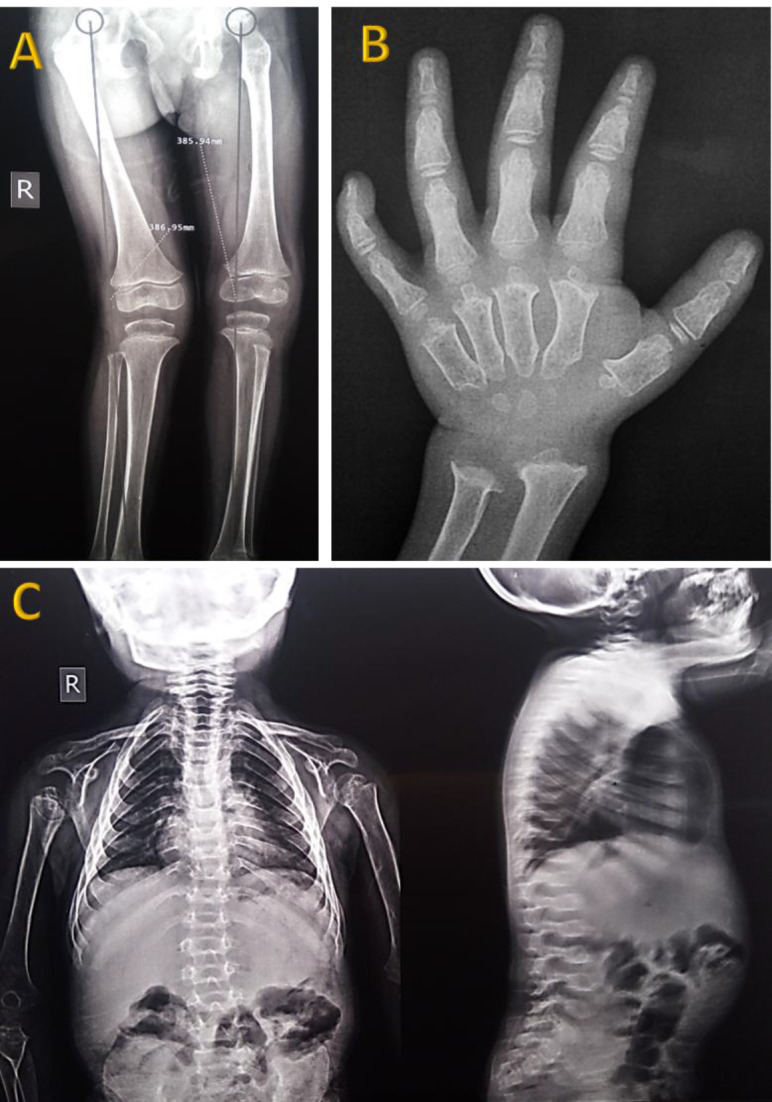

A Novel Missense Mutation of c.965C>T (p.Ala322Val) in the Human <i>GALNS</i> Gene Results in Severe Mucopolysaccharidosis Type IVA.